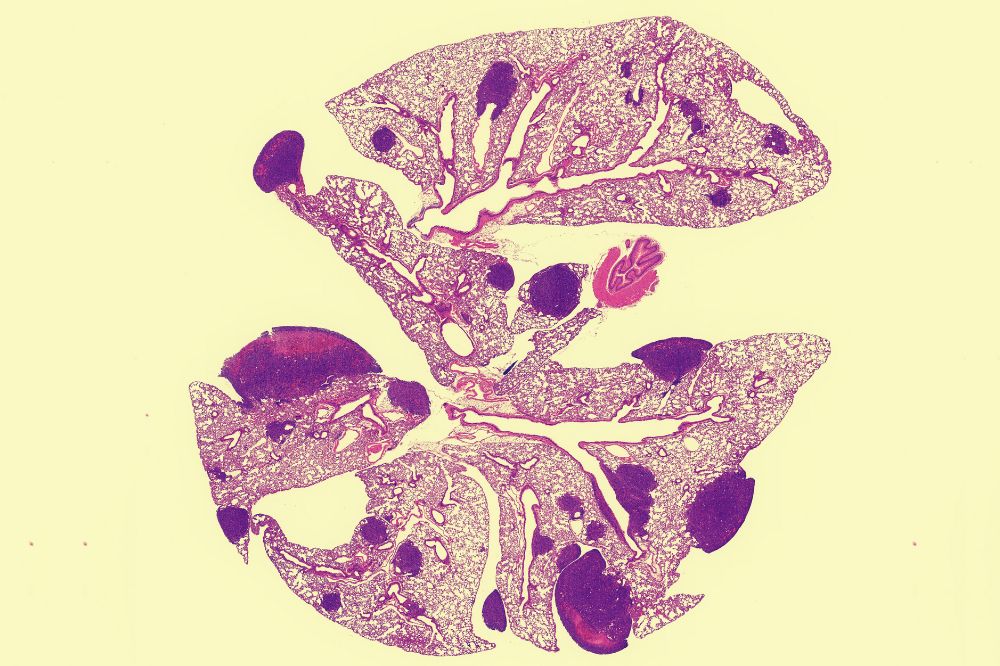

After the initial analysis implicated PCSK9, Mei acquired more patient data from Europe and collaborated with Swedish researchers who confirmed these findings in Scandinavian women with early-stage breast cancer. Mei also turned to the lab to explore the mechanisms underlying the effect on metastasis and to untangle this from the gene’s known role in cholesterol control. In experiments in mice whose genomes included the PCSK9 variant, breast tumors metastasized aggressively to the lungs. However, altering PCSK9 in tumors alone did not encourage metastasis. And while high cholesterol levels can promote cancer, feeding the animals high-cholesterol diets indicated that high LDL levels on their own also did not explain the increase in metastasis.